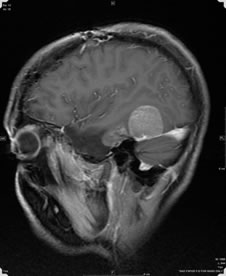

A 36-year-old man with no past medical history presented with seizures and headaches in 2004. He was found to have a right middle fossa tumor, for which he underwent two resections in 2006, with conflicting pathology reports. At that time, adjunctive therapy was advised, but the patient did not follow through. He re-presented with seizures, with recurrent tumor discovered on imaging. The neurological examination was intact, expect for right partial cranial fourth nerve palsy and right V1 to V3 numbness, which had been longstanding. The patient then had a right temporal craniotomy for resection of tumor. At surgery, the tumor was well defined and appeared to take origin from the inferior dura and the tentorium. All obvious tumor was removed, and the patient had an uneventful postoperative course. His neurological examination has been stable, and on postoperative MRI, there is no definitive residual tumor. The patient was discharged home in stable condition.